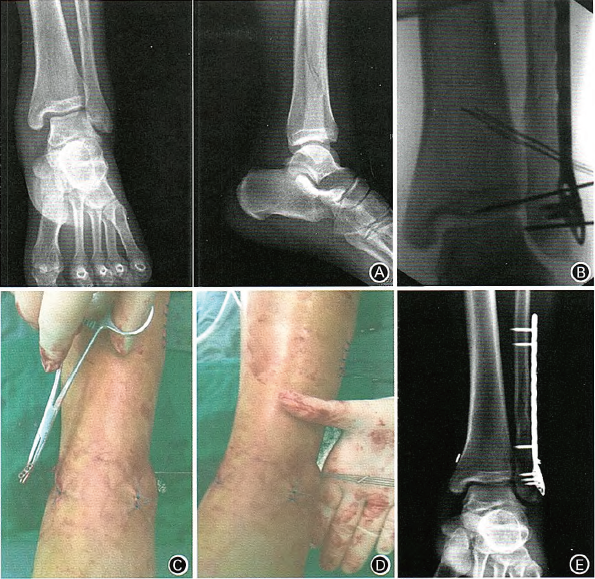

图2 Denis—Weber C型踝关节骨折合并下胫腓联合损伤,使用2枚Endobutton钢板固定。A.术前x线片示内踝间隙增宽; B.固定外踝骨折后进行外旋应力试验,透视见内踝间隙增宽,提示下胫腓联合损伤;C.胫侧Endobutton钢板;D腓侧Endobuttor钢板;E.术后x线片